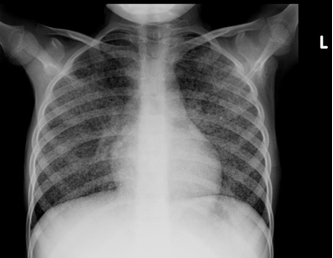

Chest x-ray is not usually diagnostic but may show bilateral diffuse parenchymal infiltrates with a “ground-glass” or reticulogranular appearance, but can be normal or have only mild parenchymal infiltrates. The earliest infiltrates are perihilar, progressing peripherally before reaching the apical portions of the lung.

Chest X-ray (CXR): TB enlarged perihilar lymph nodes are better visualised on a lateral CXR than a PA view, therefore, it is important to obtain both PA and lateral films when evaluating a child with suspected TB.